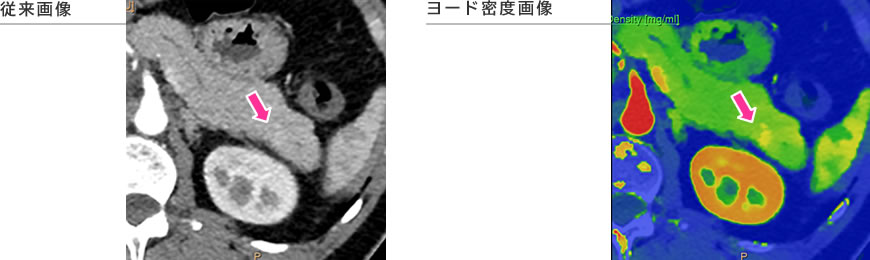

デュアルエナジーCTを活用した画像(Philips様よりご提供)

スペクトラル画像では、仮想単色X線画像、ヨード密度画像、実効原子番号画像など、さまざまな情報を持った画像が取得でき、従来のCT画像だけで判断がつきにくい病変や組織が、より明確に診断が可能となります。

膵頭部腫瘍